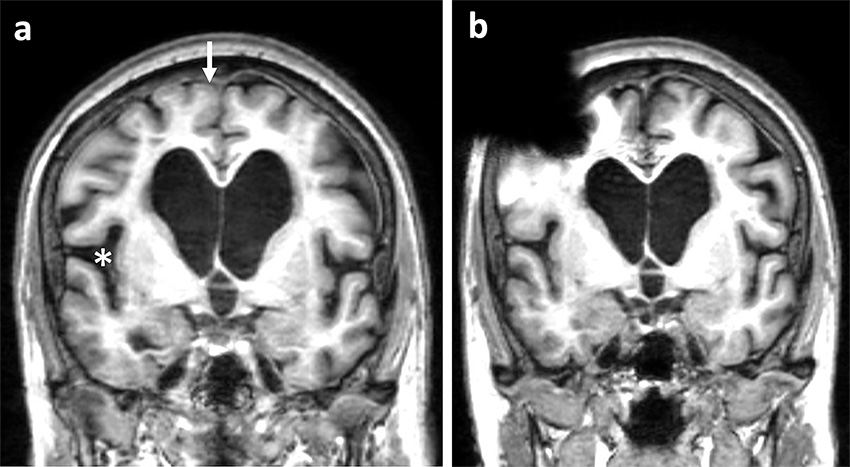

MR med FLAIR-sekvenser preoperativt (a) och 3 månader postoperativt (b) hos en patient som förbättrades kliniskt efter shuntoperation. Preoperativt uppvisade patienten så kallat DESH-fenomen (disproportionally enlarged subarachnoid spaces), det vill säga ventrikulomegali, trånga konvexitetsfåror (pil) och vidgade fissurae Sylvii (asterisk). Ventrikelvidden och Evans-index hade inte minskat signifikant mellan undersökningarna, men neuroradiologen bedömde att konvexitetsfårorna var mer öppetstående och fissurae Sylvii var mindre vidgade postoperativt. Bild (b) visar även den MR-artefakt (svart signal höger frontalt) som shuntventilen ger upphov till.